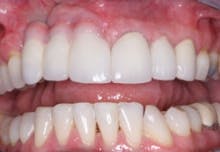

FIG. 7 — Finished restorative treatment.

When the lips of this patient are retracted, the esthetic result is unacceptable (Fig. 7). However, when the patient smiles as high as he can, the result is optimal, and he is very satisfied with his treatment (Fig. 8).

FIG. 8 — Retracted lips and patient’s smile.

In summary, each case is different. If a significant bone defect is present when implants are being considered, and the patient will accept grafting, that procedure is advisable. If the smile line or display of mandibular teeth or crowns is not objectionable, placement of gingival colored ceramic on the prosthesis can be a highly acceptable and predictable technique.